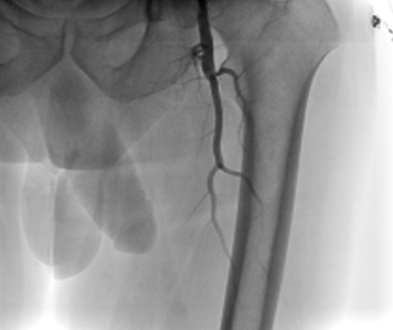

A 70-year-old gentleman with an extensive history of tobacco abuse and a non-ischemic cardiomyopathy presents with left leg claudication for the last 8 years.  His resting ABIs are right 1.00, left .80.  A 6F Ansel (Cook Medical) was selectively engaged into the common femoral artery and in spite of the fact that it was difficult to delineate the origin of the SFA, we passed the .014 Command wire (Abbott Vascular, Abbott Park, Illinois) with the CrossLock™ balloon catheter.  The FrontRunner™ was passed through the Rx port of the CrossLock™ and with the wire pulled back and the CrossLock™ balloon inflated, we were able to pass the FrontRunner™ across the total occlusion.  This was followed by balloon angioplasty and then multiple drug eluting balloons (Lutonix, Bard Peripheral, Tempe, Arizona).  Following this, there was excellent patency and runoff.

Figure 12. The CrossLock™ has been deflated, and it is advanced over the FrontRunner™.

Figure 13. The CrossLock™ and Front Runner™ were removed and a Glide catheter was passed over the .014 wire and an .035 wire is now passed in an intraluminal position.